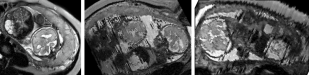

During image acquisition the fetus is not sedated and moves freely as well as the mother breathes normally. As a result, movements are likely to corrupt the scans, hiding pathology and causing overlap between different anatomical regions. In order to limit these artifacts, fast scanning sequences such as ssFSE [10] allow for the rapid acquisition of single slices at high in-plane resolution in a large field of view and good tissue contrast of the uterus. However, when acquiring a 3D volume through a stack of slices, inter-slice artifacts in the out-of-plane views are highly likely. Consequently, this restricts reliable diagnostics to individual slices in the current clinical practice. Fig. 1 depicts a typical example of motion related artifacts in a fetal single-shot fast spin echo (ssFSE) scan. The observed motion (c.f. Fig. 1 b & c) is of unpredictable nature and consists of a combination of maternal respiration movements, fetal movements and bowel movements.

Reconstruction of Fetal Organs: Exemplary PVR and SVR reconstructions under motion introduced by kicking of the fetus are shown in Fig. 11. PVR reconstruction results show an improved visual appearance and less blurring in the region with severe motion artifacts (arrow). An example of a challenging clinical case with a kidney malformation in one of twin fetuses, is shown in Fig. 8. Our clinical partners confirmed that such complications are easier to examine and to quantify after PVR-based reconstruction.